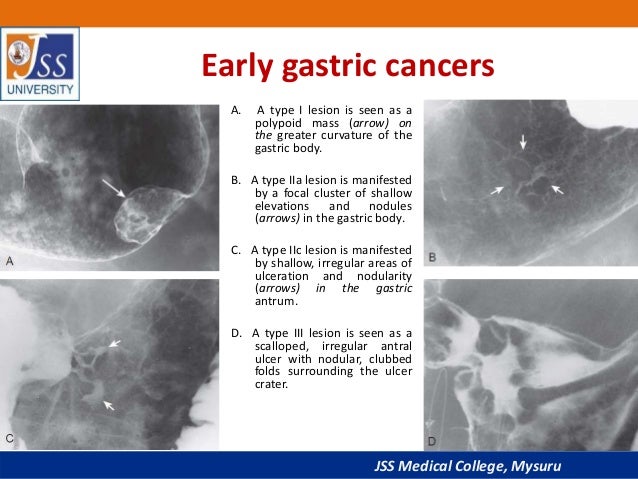

Gastric cardia radiology. Diagnostic centers of america dca is a leading diagnostic imaging facility offering a full array of imaging services in palm beach county florida. We have five state of the art radiology imaging centers in boca raton boynton beach delray beach and wellington florida. The gastric cardia is characterized on barium stud ies by three or four stellate folds that radiate to a central point at the gastro esophageal junction also known as the cardiac rosette fig 2 12. Variations and benign influences may closely resemble the more dangerous lesion.